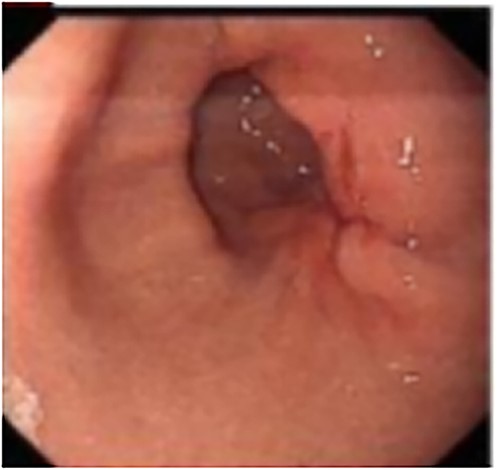

A 50-year-old Chinese man presented with right upper abdominal discomfort for 18 days. A computed tomography (CT) enhanced scan showed the thickened wall of the antrum and a cystic foci in the gallbladder bed (Fig. 1). Endoscopy revealed submucosal tumor with ulcer formation situated at the gastric antrum (Fig. 2). Pathology was positive for adenocarcinoma. His past history included hypertension, type 2 diabetes, hyperuricemia and hyperlipidemia. He had a medical history of laparoscopic cholecystectomy, performed 20 years ago for acute gangrenous cholecystitis. Physical examination revealed mild right upper epigastric tenderness.

Endoscopy revealed the mucosa of gastric antrum was rough, with convergence of the surrounding folds and deformation on the large curved side of the posterior wall. At the oral side, there was a gentle slope uplift under the mucosa, about 0.6 × 0.8 cm in size.